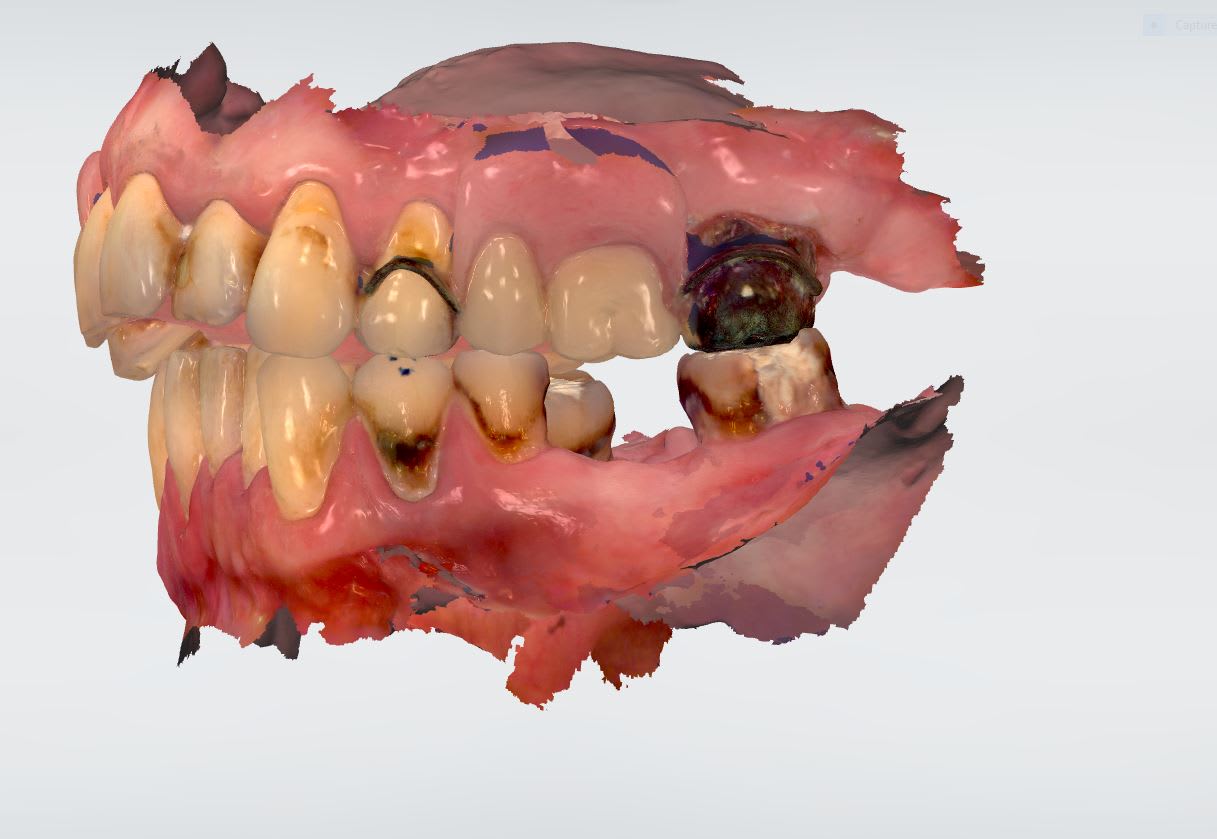

Par contre pour un cas global , comme il est il restera , ce n est pas l informatique qui va te modifier une reconstitution dans une nouvelle occlusion avec une baguette mabit .

Essayage moke up transitoire avant.

Moke up transitoire xtrudt - Eugenol